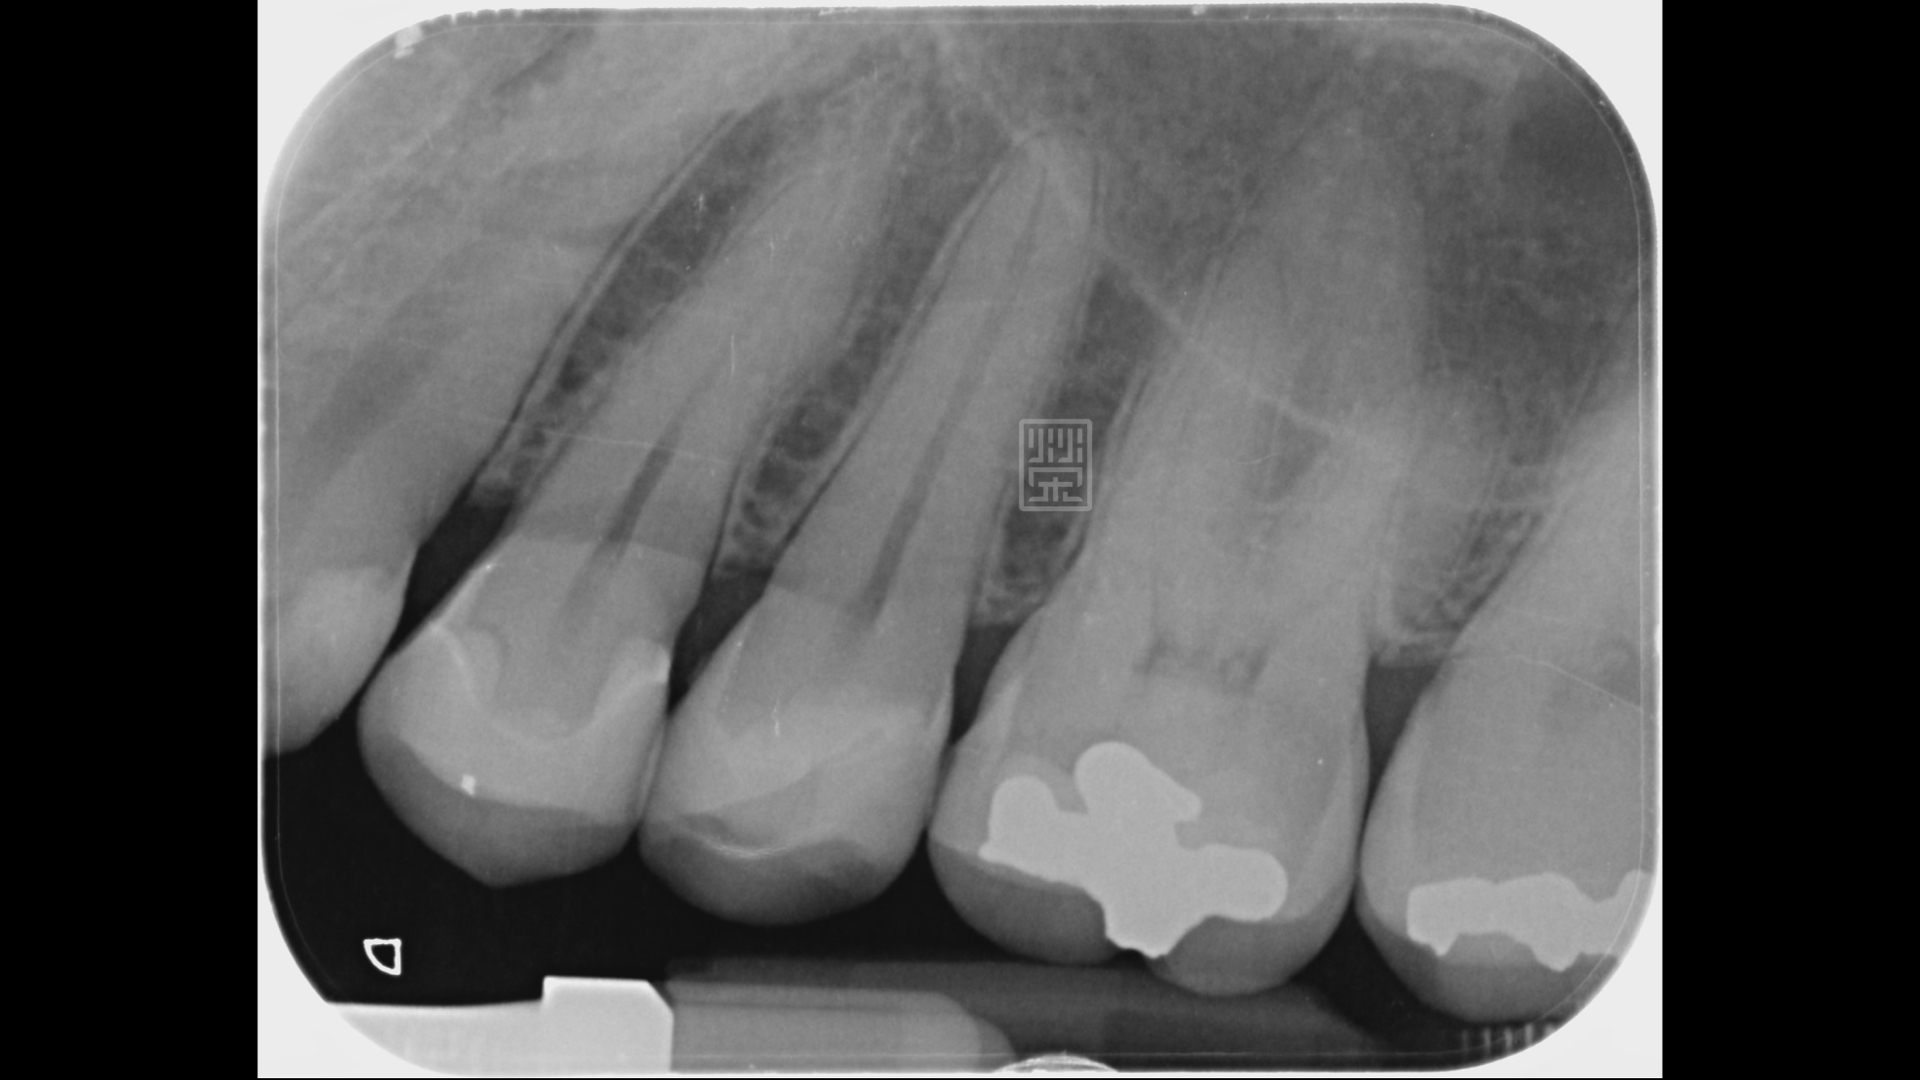

裂痕相對位置下的X光片,可以明顯發現蛀牙

早期填補牙齒時,會使用汞齊合金,俗稱銀粉的材料,但是這個材料硬化時,會有1~4%體積膨脹,會累積壓力在齒質上,長期咬合力作用下,可能會造成牙齒產生裂痕,而細菌就容易順著這個裂痕,造成牙齒蛀牙或是破壞。

所以當把銀粉清除後,發現下方的蛀牙遠比想像中的大,甚至內側牙齒只剩下薄薄的一片,加上本身口腔清潔不良,所以外側牙齒也有蛀牙,為了減少牙齒的傷害,只做局部牙齒覆蓋,盡量保留牙齒健康齒質,再將靠近牙髓部分的牙齒用複合樹脂與保護牙髓的襯墊材料保護起來後,用全瓷嵌體將牙齒恢復功能與美觀。